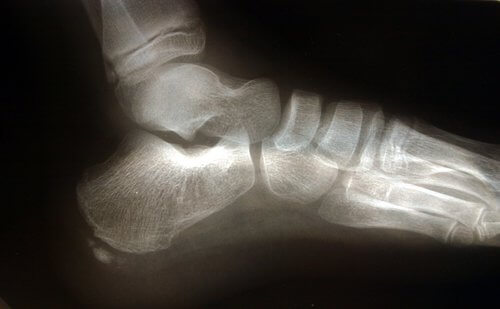

Anatomia do pé

Há várias estruturas anatômicas implicadas que podem causar a sobrecarga da fáscia plantar.

O tendão de Aquiles é um ligamento que se insere desde os músculos gastrocnêmios, comumente chamados gamelos, e o sóleo até o osso do calcanhar. Uma retração do tendão de Aquiles causará um aumento de pressão no calcâneo, com o consequente aumento de pressão no ligamento arqueado.

Outro fator a levar em conta na estrutura anatômica é o apoio do pé, ou seja, a forma como o pé toca o chão. Os pés planos ou com tendência pronadora causam um alongamento maior da fáscia plantar, aumentando o risco de rupturas pelo aumento da pressão no tecido.